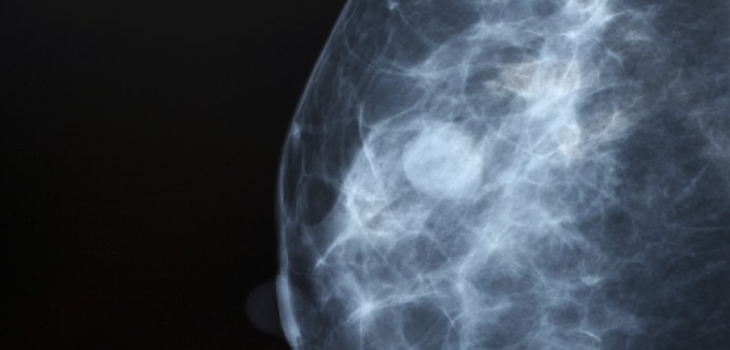

유방을 단면으로 보면, 유선이 복잡하게 얽혀 있고 그 사이를 지방 조직이 감싸고 있습니다. 지방은 영상 검사에서 어둡게, 유선은 밝게 보이는데, 치밀유방의 경우 밝은 부분이 넓게 퍼져 있습니다. 이런 이유로 의학 영상에서는 유방이 전체적으로 ‘하얗게’ 보이는 특징이 있습니다.

유방촬영(맘모그래피)에서는 유선 조직이 많을수록 하얗게 보입니다. 문제는 혹이나 종양도 같은 흰색으로 나타난다는 점입니다. 이 때문에 치밀유방에서는 이상 병변이 가려질 가능성이 있어 영상의학과에서는 이를 별도로 표시합니다. 하지만 이 결과만으로 질병을 판단하지는 않으며, 정확한 평가는 초음파나 다른 검진 결과와 함께 종합적으로 이뤄집니다.